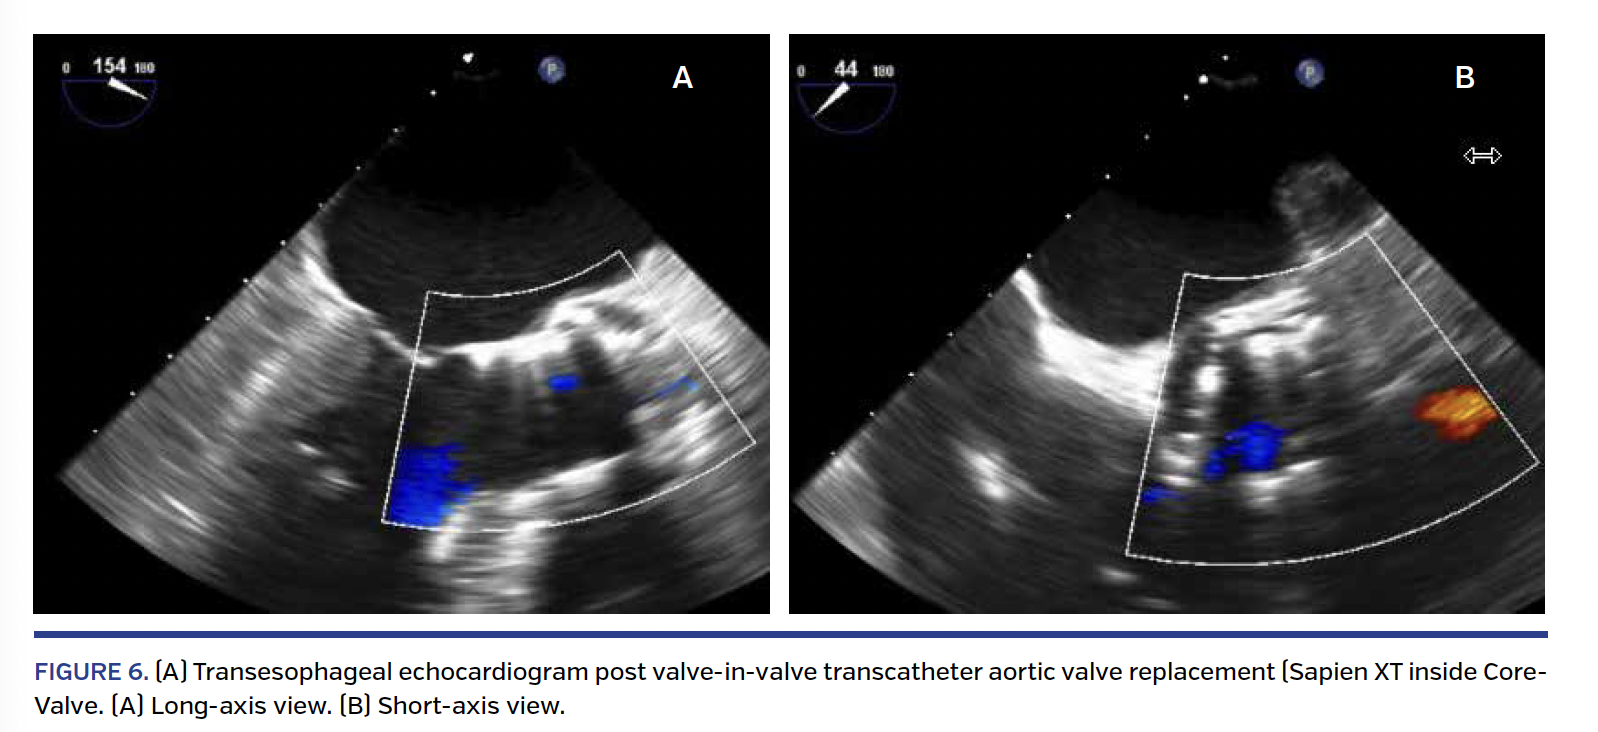

Second TAVR. As with the first TAVR procedure, the second TAVR procedure was completed under general anesthesia via transfemoral route. TEE was also used to guide the procedure. No dilation of the first TAVR valve was planned. The Sapien XT valve was prepared as usual but with an additional 2 cc of volume in the balloon. The CoreValve was crossed without difficulty and a properly curved extra-stiff Amplatzer wire was advanced into the left ventricle. The Sapien XT valve was prepared and advanced across the CoreValve without difficulty. The positioning was set at a level of 2-4 mm from the lower edge of the CoreValve. With proper positioning, rapid pacing was initiated. At a systolic blood pressure <50 mm Hg and pulse pressure <10 mm Hg, the Sapien XT valve was deployed slowly and remained in the targeted position (Figure 5). TEE immediately post TAVR showed resolution of the central aortic regurgitation. In addition, there was near complete resolution of the PVL (Figure 6). A follow-up aortogram demonstrated that the coronary arteries were widely patent, as well as a significant reduction in his mitral valve regurgitation (Figure 7).